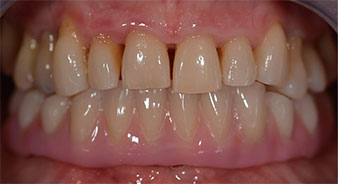

The 64-year-old patient presented with residual dentition of teeth 38, 33 and 43 and a clasp denture in the mandible (Fig. 1 and 2).

Fig. 1